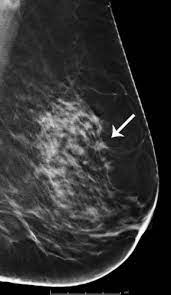

This post looks at microcalcifications, dcis and malignant breast cancer. In this case, negative means nothing bad was found. Mammogram — comprehensive overview covers definition, risks, what to expect, and results how often you should have a mammogram depends on your age and your risk of breast cancer. Did you know that a mammogram actually delivers cancer causing radiation? All women in england diagnosed early public health england is still nudging women to attend mammogram appointments. Breast cancer often is found by a woman herself. Breast cancer screening tools are used to find breast cancer in a woman with no warning signs or symptoms. Six previous radiologists failed to find the cancer in routine mammograms.credit.northwestern artificial intelligence can help doctors do a better job of finding breast cancer on mammograms there are many radiologists who are reading mammograms who make mistakes, some well outside. All about the mammogram report. Most women never hear about the risk of cancer from this procedure. The earliest sign of breast cancer can be an abnormality depicted on a mammogram, before it can be felt by the woman or her physician. Some women find it painful. Small white specks are usually harmless.

Most breast cancers are discovered by women during regular daily activities like bathing, shaving or scratching. Did you know that a mammogram actually delivers cancer causing radiation? The earliest sign of breast cancer can be an abnormality depicted on a mammogram, before it can be felt by the woman or her physician. This is because the most aggressive breast cancers are found in dense breast tissue, which mammograms perform poorly on.8. But you can prepare yourself with critical information before you get a mammogram. All women in england diagnosed early public health england is still nudging women to attend mammogram appointments. Not all of the tumors found by mammography can be cured. More data is pointing in that direction. Finding breast cancer early may not reduce a woman's chance of dying from the disease. This happens in almost one half of all cases of breast cancer in mammogram: The most common sign of breast cancer is a new lump or mass in the breast. This chapter reviews breast cancer risk factors, signs, and symptoms of breast cancer, the normal mammogram, mammographic findings of breast cancer, basic interpretation of screening mammograms, and workup of findings detected at screening with additional mammographic views. Breast cancer screening tools are used to find breast cancer in a woman with no warning signs or symptoms.

Mammograms are not yet been said to cause breast cancer. Webmd explains how mammograms are performed and why they're important in detecting breast mammography can be your best defense against breast cancer because it can often spot the not all breast cancers can be found on mammograms, especially in younger women who have more. The earliest sign of breast cancer can be an abnormality depicted on a mammogram, before it can be felt by the woman or her physician. Do you have an abnormal mammogram? This chapter reviews breast cancer risk factors, signs, and symptoms of breast cancer, the normal mammogram, mammographic findings of breast cancer, basic interpretation of screening mammograms, and workup of findings detected at screening with additional mammographic views.